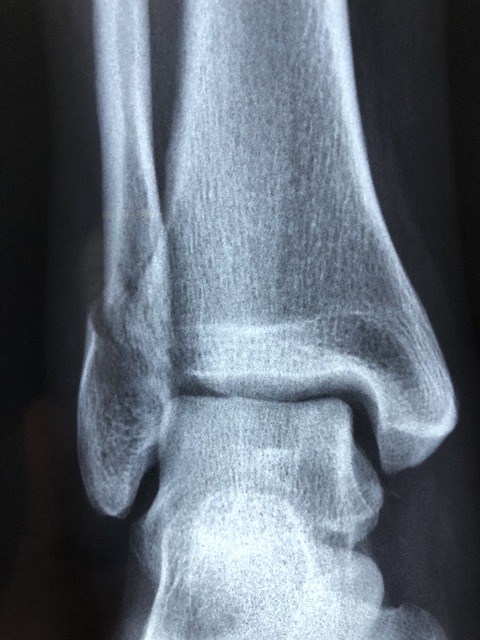

5. 발목 골절

발에 금이가 거나 골절된 경우 통증을 유발할 수 있습니다. 운동을 하거나 걷다가 발을 잘못 접질릴 때 발목 인대가 늘어나거나 뼈에 이상이 생겨 통증을 유발하게 됩니다. 발목에서 시작된 통증이 발뒤꿈치까지 이어질 수 있습니다. 발목이 골절된 경우에는 서있기도 힘들고 손으로 누를 때에 심한 통증을 유발하게 됩니다.